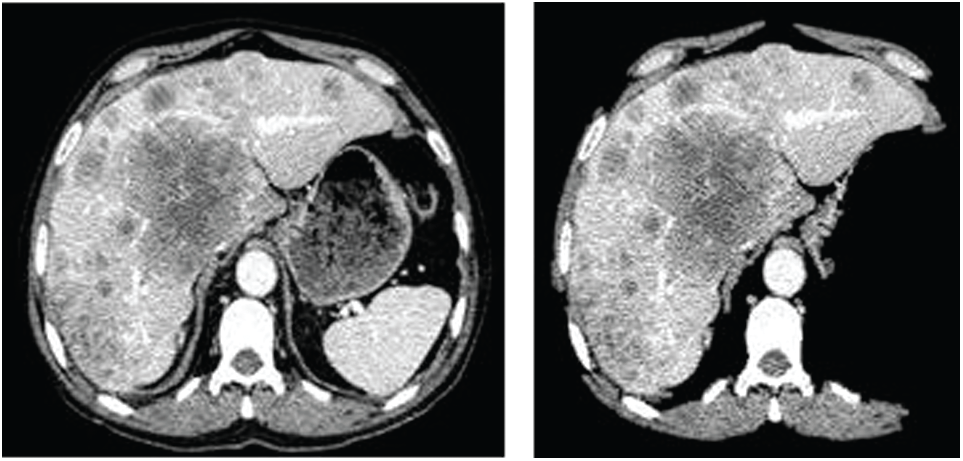

The images in Fig. 2 present the outcome of the proposed approach for removing the non-liver artifacts from the image. On removing the non-liver artifacts from the CT scan image, assessing the affected region would be easy. IT also enhances the approximated outcomes accuracy in determining the irregularity’s impact. Moreover, the anomaly is being recognized based on the intensity at the particular impacted region. The non-liver artifacts may sometimes lead to the misinterpretation of the non-tumorous region as the tumorous region. And this phase is considered to be one of the pre-processing stages in approximating the damaged region.

Figure 2: The outcome image on removing the non-liver artifacts